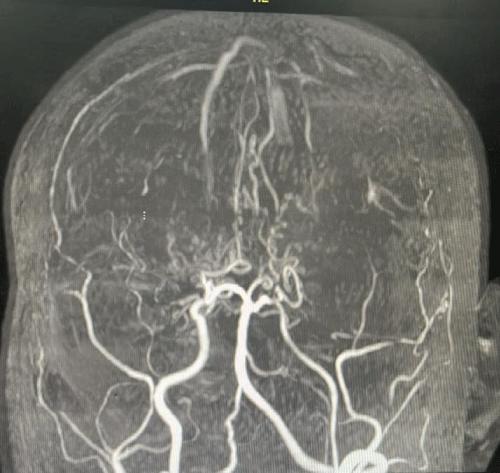

Article ID: wjnp.2026.b1906

Ureteric Fibroepithelial Polyp in a Child-Recurrent Presentations and Diagnostic Dilemma

Swamy KB 1 Govani DR 2 Mehta AR 3 Midha PK 3 Govani ND 2 Panchasara NG 2 Patel RR 2 Patel RV* 2

Benign ureteral polyps, also known as fibroepithelial polyps, can cause upper urinary tract obstruction by growing to block the flow of urine from the kidney. Fibroepithelial polyps are very rare benign lesions originating from the mesoderm. We have presented an interesting and unusual case who presented with recurrent right sided abdominal colicky pain and vomiting. During investigation was found an underlying cause of right sided abdominal intermittent pain at the right pelviureteric…